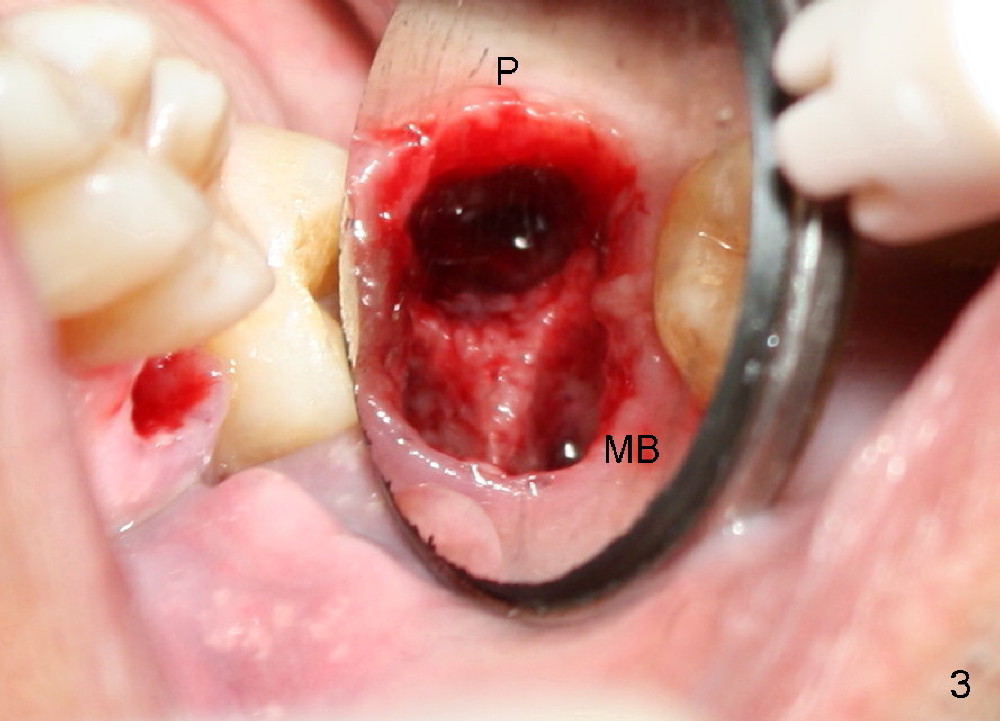

The tooth #3 has a crack line (Fig.1 ^). The septum (Fig.2 S) looks like an inverted pyramid (Fig.3), coronal part being pointed, whereas the apical broad. The shape of the septum is not so favorable to placement of tapered implant. Osteotomy starts with 1.5 mm pilot drill in the middle of the septum, followed by round tapered osteotomes 2 and 3 mm. The osteotomy begins to deviate into the mesiobuccal socket. The same osteotomes are used to re-direct the osteotomy palatally, followed by tapered drills, trying to move osteotomy palatally. A 4.5x17 mm tap is inserted with stability (Fig.4). Following using 5x17 mm tap at the depth of 12 mm, a 5.3x12 mm bone-level implant is placed ~ 1.5 mm below the crest, 1.5 mm above the septum (Fig.5). Demineralized cortical human allograft is placed in the remaining sockets and around the most coronal aspect of the implant (with a small piece of gauze placed in the implant well). After removal of the gauze, a piece of collagen membrane is pierced and carried by a 8.2x4/3 mm healing abutment and fixed in place (Fig.6 M). The periphery of the membrane is tucked underneath the gingiva. The wound is covered by perio dressing. The patient returns to clinic for follow up 8 days postop. There is no discomfort. In order to protect the collagen membrane (Fig.6), the perio dressing is intentionally not removed (Fig.7). Two weeks postop, the patient remains asymptomatic. After perio dressing removal, the membrane appears to have been resorbed (Fig.8 as compared to Fig.6). The bone graft (B), although exposed, remains in place and condensed, surrounded by healing healthy gingiva (*). The patient returns 2.5 months postop. The implant appears to osteointegrate (Fig.9, as compared to Fig.5). The buccal (Fig.10) and palatal (Fig.11) gingiva adapts to the healing abutment. When the healing abutment is removed for restoration 3 months postop, the gingiva looks healthy (Fig.12). A cemented abutment (5.8x4(2) mm) is placed; a crown is fabricated (Fig.13). The patient returns for recall 5 months post cementation. He reports food impaction distal to the crown. The gap mesial to the implant has closed (Fig.14).